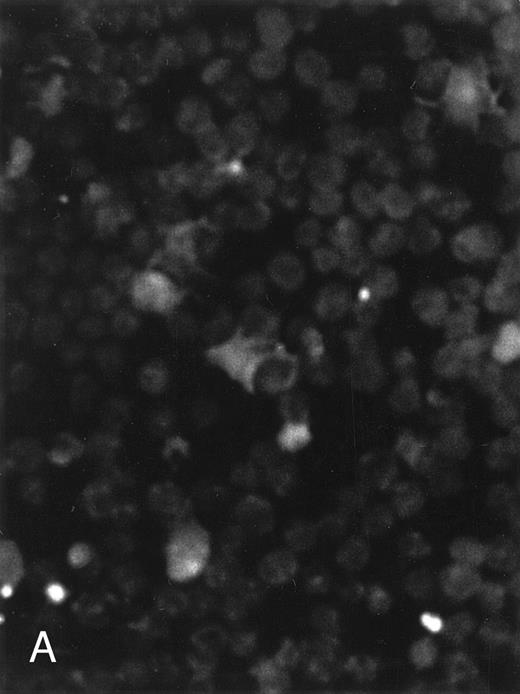

The apoptosis-specific genomic DNA cleavage was also assessed by the TUNEL (TdT-mediated dUTP nick end labelling) assay (In situ Cell Death Detection Kit, AP; Boehringer Mannheim). PLB-985 cells were treated with 10−6 mol/L 9-cis-RA for 3 days and assayed for DNA strand breakage. Control cells growing exponentially showed very limited fluorescent labeling, whereas RA-treated cells showed numerous positive cells (Fig 4). These results confirmed that RA induced specific DNA strand breakage in PLB-985 cells, indicative of the apoptotic process.

Induction of genomic DNA-nicking in apoptotic PLB-985 cells treated with 10−6 mol/L 9-cis-RA for 3 days. Cytospins were prepared from (A) normal and (B) RA-treated cells, and the TUNEL assay was performed, labeling the apoptosis-specific DNA strand breaks with fluorescent label as described in Materials and Methods.